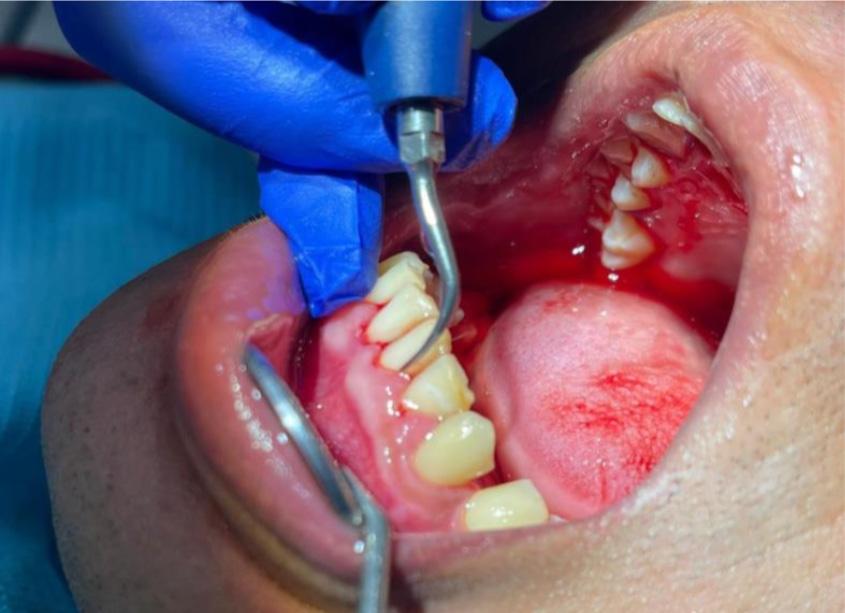

Apa itu rawatan penskaleran gigi?

Pernahkah anda ke mana-mana Pusat Pergigian Angkatan Tentera (PGAT) atau ke klinik pergigian di mana ramai doktor gigi menasihatkan anda untuk melakukan penskaleran gigi yang juga dikenali sebagai scaling? Penskaleran adalah prosedur menghilangkan tartar (plak yang mengeras) dan kotoran yang melekat pada gigi anda kesan daripada makanan, rokok atau teknik pemberusan yang kurang efektif. Rawatan ini adalah salah satu cara untuk mencegah dan merawat penyakit gusi jika doktor gigi telah mengesahkan anda mempunyai plak pada gigi.

Apa yang terjadi sewaktu rawatan penskaleran?

Jangan panik! Rawatan ini adalah termasuk rawatan rutin yang perlu dilakukan sekurang-kurangnya 2 kali setahun bagi mengelakkan penyakit gusi. Sepanjang

rawatan, doktor akan menggunakan ‘scaler’ untuk menghilangkan tartar dan kotoran pada gigi anda. Bagi yang tidak pernah melakukan rawatan ini akan merasa kurang selesa namun begitu, anda boleh mendapatkan rawatan ini bersama-sama ubat bius dari doktor gigi.

Apakah yang terjadi selepas rawatan penskaleran ini?

Anda akan merasa mulut dan gigi lebih bersih dan licin berbanding sebelum rawatan. Terdapat beberapa pesakit menyatakan mereka merasa lubang atau ruang di celah-celah gigi yang sebelum ini tidak pernah wujud akan terasa di ruang tersebut. Untuk pengetahuan umum, Tuhan telah menciptakan sesuatu sebaikbaik kejadian termasuklah ruang di antara gigi bagi memudahkan aliran air liur dan makanan. Air liur bukan sahaja bertugas sebagai ‘pelincir’ apabila kita makan, tetapi juga mempunyai sifat anti bakteria yang boleh mencuci dan membunuh kuman bahaya dalam mulut.

Oleh kerana makanan sering berada di celah-celah atau ruang di antara gigi, lama kelamaan makanan tersebut menjadi tartar dan tidak dapat dicuci menggunakan berus gigi biasa. Maka dengan itu, lama-kelamaan ruang tersebut tertutup dan anda akan merasakan tiada ruang dicelah permukaan gigi. Setelah rawatan penskaleran ini dilakukan, kesihatan gusi anda akan menjadi lebih baik dan anda akan merasakan tanda-tanda penyakit gusi seperti gusi mudah berdarah sewaktu memberus gigi akan berkurangan.

OLEH Maj (Dr) Tengku Natasha Eleena binti Tengku Ahmad Noor (801 RSAT Kem Penrissen)Apakah yang akan terjadi jika tidak melakukan rawatan penskaleran?

Tartar dan kekotoran pada gigi dan gusi anda akan menyebabkan keradangan pada gusi kerana lama kelamaan tartar akan berkumpul ke dalam gusi seterusnya merosakkan gusi dan tulang yang menyokong gigi anda. Mengikut American Academy of Periodontology, tanda-tanda anda mengalami penyakit gusi adalah:

• Gusi merah, bengkak atau sakit lain di dalam mulut anda.

• Pendarahan semasa memberus gigi, menggunakan flos atau makan makanan keras.

• Gusi menjadi surut dari gigi yang menyebabkan gigi kelihatan lebih panjang daripada sebelumnya.

• Gigi menjadi longgar atau goyang.

• Nanah di antara gusi dan gigi.

• Terdapat seperti luka di mulut.

• Nafas berbau yang berterusan.

• Perubahan pada gigi anda apabila anda menggigit.

• Perubahan pada kesesuaian gigi palsu jika anda memakainya.

Penyakit gusi adalah termasuk penyakit yang senyap dan kebanyakan pesakit tidak merasa sakit sehingga penyakit ini menjadi lebih rumit. Rawatan penskaleran amat penting dalam mencegah penyakit gusi. Namun begitu, penjagaan kesihatan pergigian di rumah juga penting seperti memberus gigi 2 minit 2 kali sehari dan mengamalkan penggunaan flos atau berus ‘interdental’ yang boleh didapati di mana-mana farmasi berdekatan.

Sebelum rawatan penskaleran Selepas rawatan penskaleran Keadaan gigi yang tidak pernah melakukan rawatan penskaleran. (A) menunjukkan tartar yang berkumpul pada gusi (B) gusi berwarna merah, bengkak dan lembut seperti span (C) gigi kelihatan lebih panjang dan bergoyang akibat penurunan gusi dan tulangLUMUT, 10 Oktober 2023 - Sambutan Hari